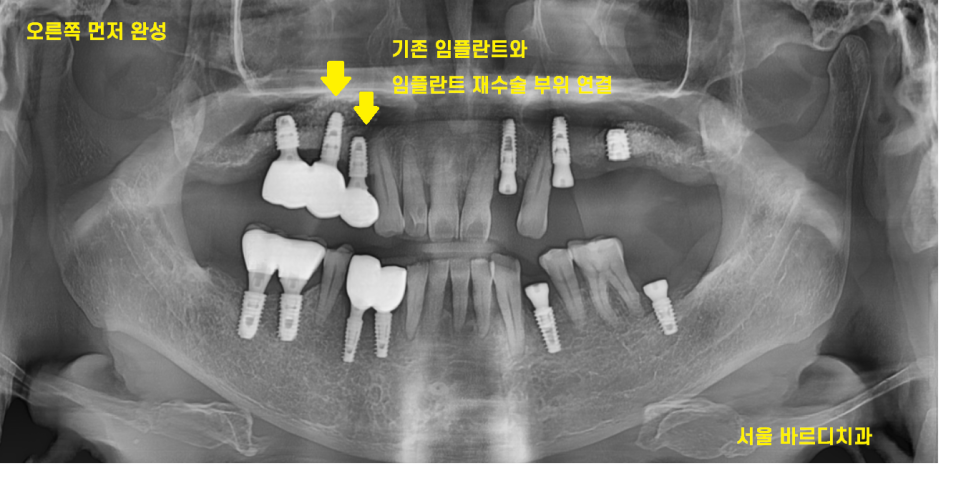

23.11.03

뼈가 좋은 오른쪽 먼저 치아를 완성했습니다.

기존 1개 살린 임플란트와

임플란트 제거 후 재식립한 부분을 연결하여

완성했습니다.

24.01.22

뼈가 약해서 조금 더 기다린 오른쪽도

마저 완성을 한 모습입니다.